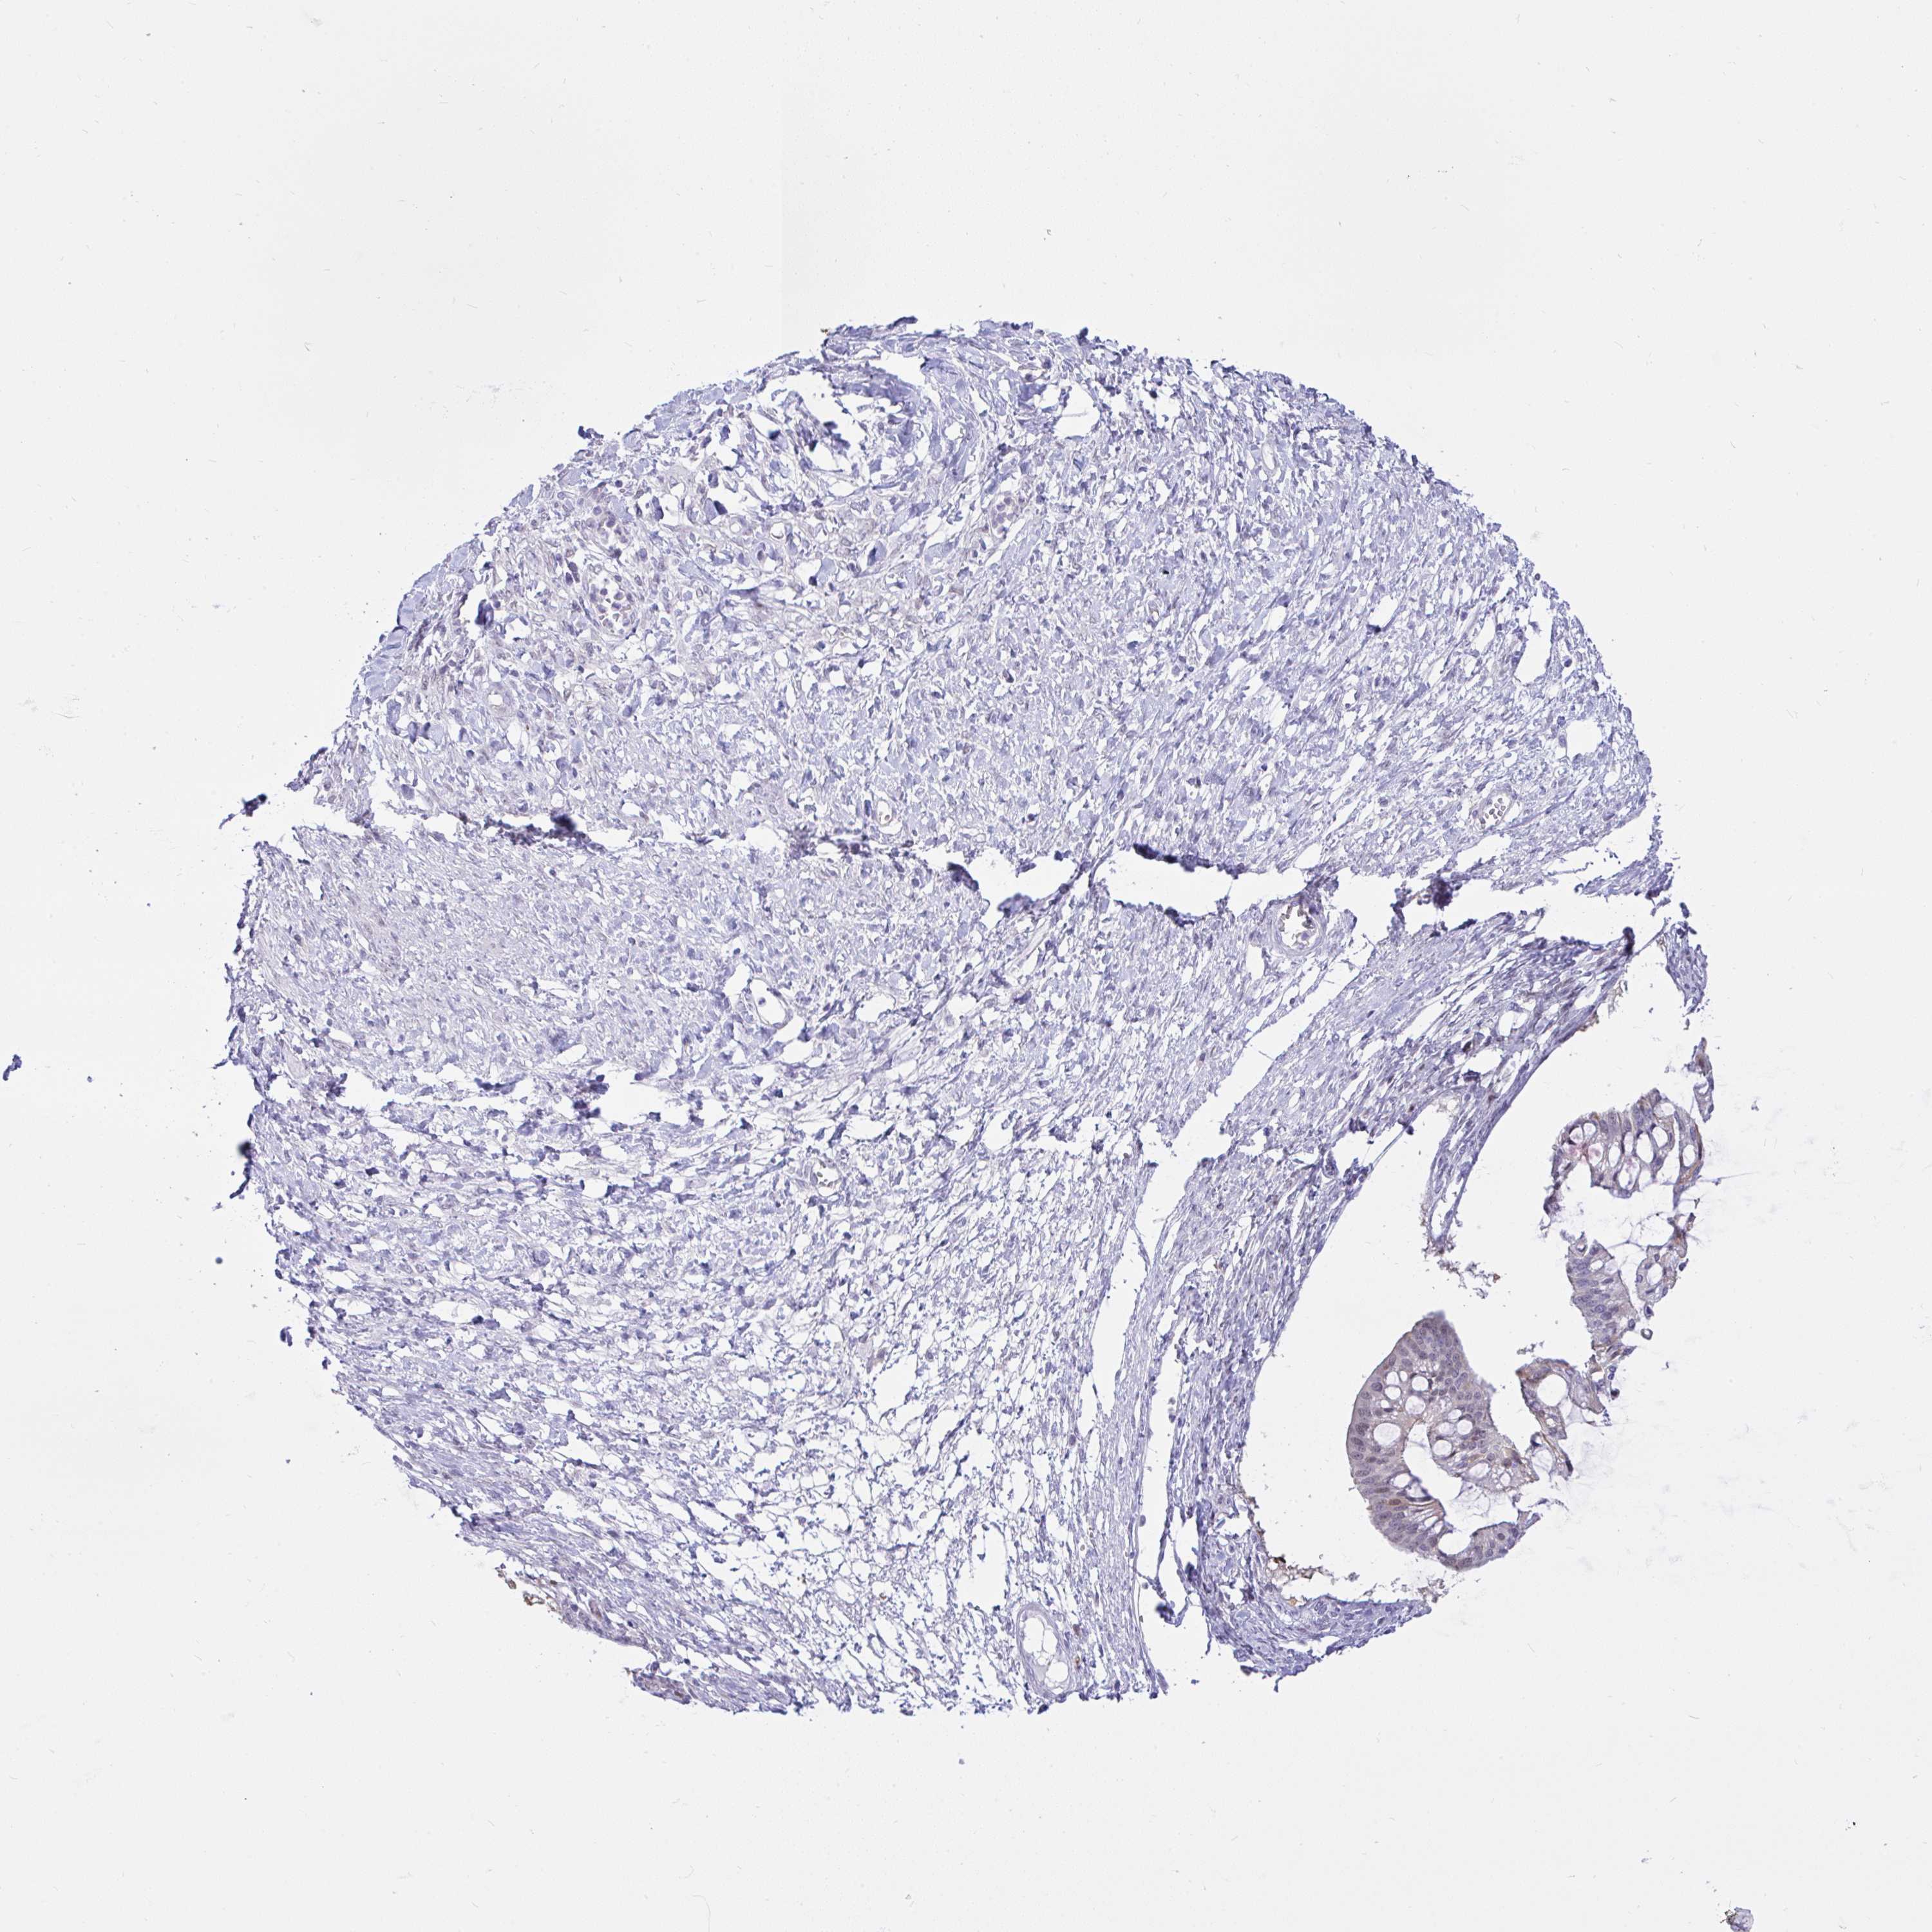

OVARIAN CANCER - Protein expressioni

A mouse-over function shows sample information and annotation data. Click on an image to view it in a full screen mode. Samples can be filtered based on level of antibody staining by selecting one or several of the following categories: high, medium, low and not detected. The assay and annotation is described here.

Note that samples used for immunohistochemistry by the Human Protein Atlas do not correspond to samples in the TCGA dataset.

Antibody stainingi

Antibody staining in the annotated cell types in the current human tissue is reported as not detected, low, medium, or high, based on conventional immunohistochemistry profiling in selected tissues. This score is based on the combination of the staining intensity and fraction of stained cells.

Each image is clickable and will lead to virtual microscopy that enables deeper exploration of all samples and also displays staining intensity scores, fraction scores and subcellular localization as well as patient and tissue information for each sample.

Antibody HPA059356

Staining

High

Medium

Low

Not detected

Intensity

Strong

Moderate

Weak

Negative

Quantity

>75%

75%-25%

<25%

None

Location

Nuclear

Cytoplasmic/membranous

Cytoplasmic/membranous,nuclear

Cystadenocarcinoma, serous, NOS

Carcinoma, endometroid

Cystadenocarcinoma, mucinous, NOS

Carcinoma, NOS